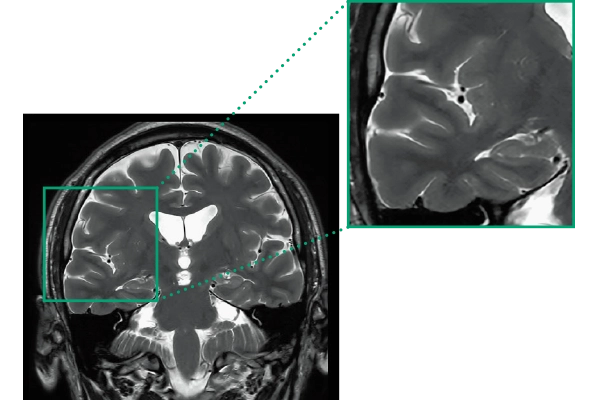

DLR offers 2 options

High Resolution

T2WI, 0.56×0.70×3.0mm, 2:28

ShortScan

FLAIR, 1:14

DWI, 0:36

3DTOF MRA (MIP), 1:26